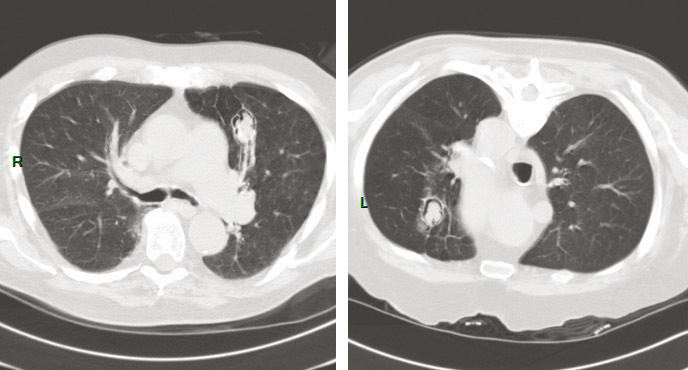

© Sylvain Poirée - La Revue du Praticien Aspergillome pulmonaire en décubitus et procubitus montrant la déclivité de la boule fungique.